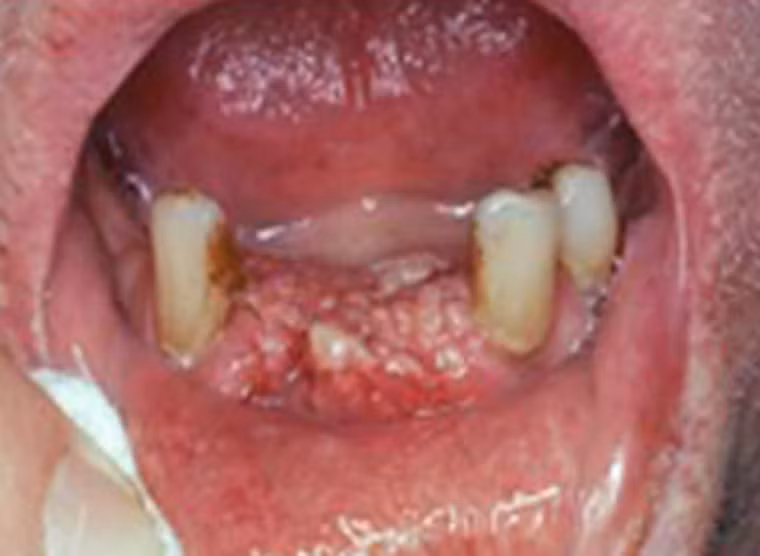

Còn đây là trường hợp của một bệnh nhân 55 tuổi, phần nướu bị tấn công bởi những khối u sần nhỏ, nó mở rộng phạm vi nhanh chóng, đặc biệt là khu vực môi dưới.